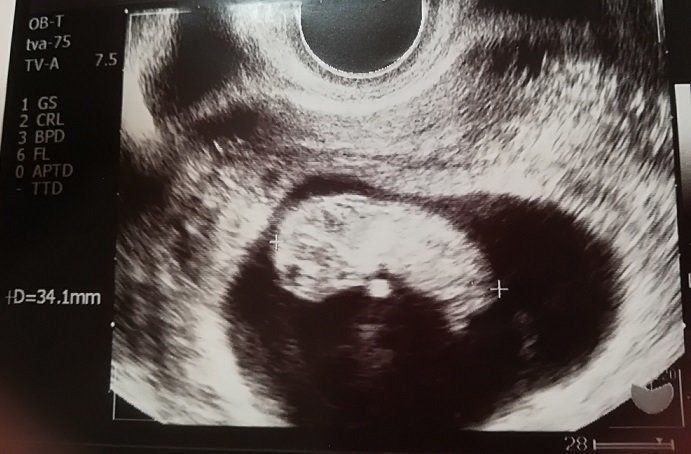

小吉さんの妊娠9週目のエコー写真

赤ちゃんは2.8cmになりました。ハート型のように写っている胎嚢の右側にあるのが頭で左側が体です。人間らしくなってきたのが嬉しかったのを覚えています。マクロビオティックの先生からいただいたアドバイスを元に、食事内容や体を冷やさないことなどに注意をしながら慎重に毎日を過ごしていました。